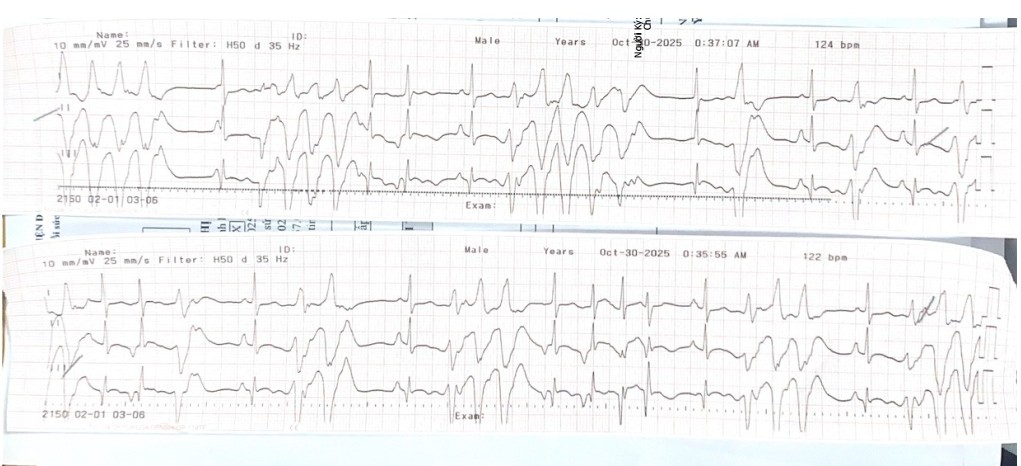

Ngay lập tức, ê-kíp cấp cứu đã tiến hành đặt ống nội khí quản, thở máy xâm nhập. Trong quá trình này, tim bệnh nhân liên tục xuất hiện các cơn rối loạn nhịp nguy hiểm như nhanh thất, rung thất, xoắn đỉnh, dẫn đến ngừng tuần hoàn. Các bác sĩ phải liên tục sốc điện, chuyển nhịp và dùng nhiều loại thuốc chống loạn nhịp để “hồi sinh” nhịp đập cho người bệnh.

Sau hội chẩn đa chuyên khoa khẩn cấp, bệnh nhân được chuyển đến khoa Hồi sức tích cực – Chống độc (HSTC – CĐ) ngay trong đêm 29/10. Tại khoa HSTC – CĐ, tình trạng rối loạn nhịp và ngừng tuần hoàn tiếp tục tái diễn nhiều lần. Bệnh nhân đã được điều trị tích cực và cấp cứu ngừng tuần hoàn thành công. Đến ngày 30/10, người bệnh được rút ống nội khí quản và chuyển về Trung tâm Tim mạch để điều trị tiếp.

Trong quá trình điều trị tại Trung tâm Tim mạch người bệnh còn trong tình trạng rất nặng, xuất hiện tái phát nhiều cơn nhịp nhanh thất, rung thất gây ngừng tuần hoàn – viêm phổi – suy tim với chức năng tâm thu thất trái giảm nhiều (EF 25%). Tại Trung tâm Tim mạch các bác sĩ, điều dưỡng đã tiến hành hồi sức, theo dõi, điều trị, chăm sóc tích cực cho người bệnh gần 30 ngày, để giúp người bệnh ở trạng thái phù hợp để có thể cấy máy phá rung tự động.

Các bác sĩ Trung tâm Tim mạch nhận định: Mặc dù đã được điều trị suy tim và chống rối loạn nhịp theo phác đồ tối ưu, tình trạng của bệnh nhân vẫn không ổn định, các cơn nhanh thất và rung thất vẫn tiếp tục xuất hiện, cho thấy nguy cơ đột tử rất cao. Khi các phác đồ điều trị nội khoa tối ưu trở nên “bất lực”, các bác sĩ đã tiến hành hội chẩn và đi đến quyết định: Thực hiện cấy máy phá rung tự động (ICD) – một giải pháp dự phòng đột tử cho bệnh nhân suy tim hiện đại nhất hiện nay.

Ca can thiệp quan trọng này được thực hiện vào sáng ngày 27/11 trên hệ thống chụp mạch số hóa xóa nền DSA hiện đại của Bệnh viện. Quá trình thực hiện, các bác sĩ tạo đường vào mạch máu, đưa các điện cực vào buồng tim một cách chính xác. Sau đó, máy ICD được cấy vào và cài đặt để tối ưu hóa quá trình vận hành. Máy ICD hoạt động như một “vệ sĩ” 24/7, có khả năng nhận biết tự động các cơn rối loạn nhịp nguy hiểm. Khi phát hiện các cơn rối loạn nhịp nhanh như trường hợp bệnh nhân đang bị, máy sẽ lập tức tạo nhịp vượt tần số hoặc tự động sốc điện, chuyển nhịp ngay lập tức, ngăn chặn nguy cơ đột tử tim.